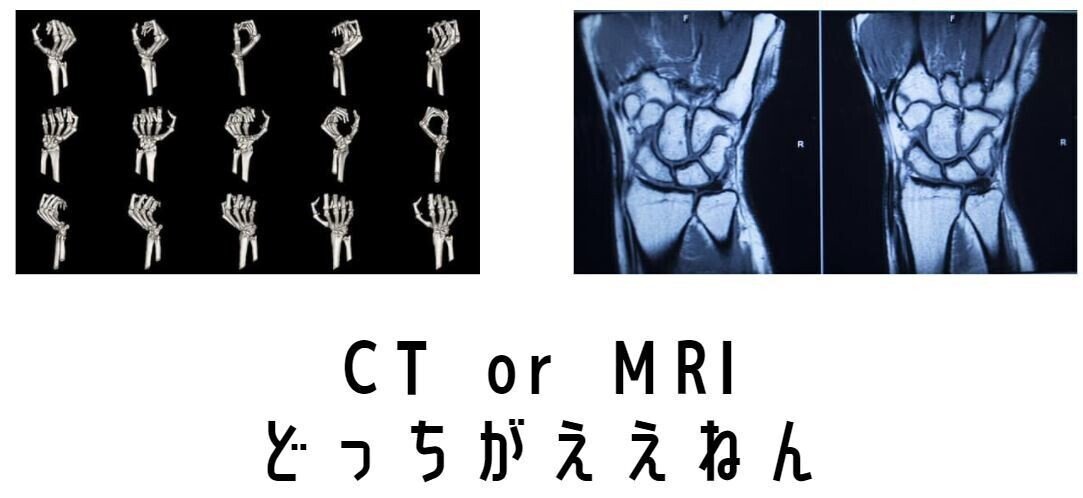

・XpとCTとMRI・・・

XpとCTとMRI・・・

CT・MRI

実は両者は大きな差はなかったりします

でも

CTでもわかりにく

不顕性骨折や骨挫傷がわかる

MRIがゴールデンスタンダードでは?

たしかにそうなんですが

文献には大多数でどの検査よりも有用であり

ランニングコストがかかる以外は

CTの放射線被ばくと違い

人体には何のデメリットもありません

だがしかし